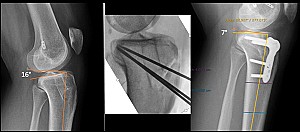

La tecnica chirurgica originale di deflexion osteotomy, descritta da Henri Dejour ad inizio degli anni ’90, prevedeva la rimozione di un cuneo osseo con base anteriore, in gergo specialistico osteotomia di sottrazione anteriore di tibia. Tramite un’incisione anteriore al ginocchio, veniva isolato il tendine rotuleo e per mezzo di osteotomi e sega oscillante si rimuoveva, posteriormente ad esso, il cuneo osseo. L’altezza della base del cuneo corrispondeva al grado di correzione applicata (circa 1 mm per ogni grado di correzione). L’osteotomia veniva infine sintetizzata con due cambre metalliche e l’intervento proseguiva eventualmente con la revisione legamentosa. Sebbene nella sostanza la tecnica sia rimasta la stessa, negli ultimi anni sono notevolmente migliorate le tecniche di pianificazione della correzione (digitali, 3D, personalizzate) e sono nate placche da osteosintesi dedicate, che consentono una fissazione stabile, un recupero del carico più rapido e permettono di diversificare la sede dell’osteotomia a seconda della specificità clinica e della preferenza del chirurgo (sovratuberositarie, retrotuberositarie, sottotuberositarie).

A) Caso di aumentato slope tibiale in esiti di pregressa ricostruzione del legamento crociato anteriore; B) Posizionamento dei fili guidi per l’ostetomia di riduzione dello slope; C) Risultato post-operatorio dopo osteosintesi con placca dedicata